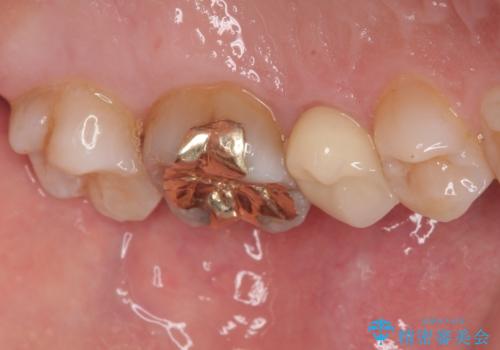

詰め物や被せ物は、精度が低いと隙間から虫歯(=二次う蝕)になりやすいという問題があります。

精度の高い補綴物を選ぶことで、将来的な治療回数を減らし、歯を長く守ることが可能です。